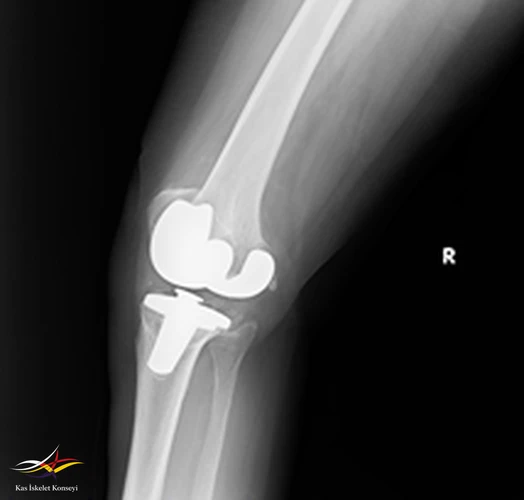

Resim 2. Revizyon ameliyatı öncesi lateral direkt grafi.